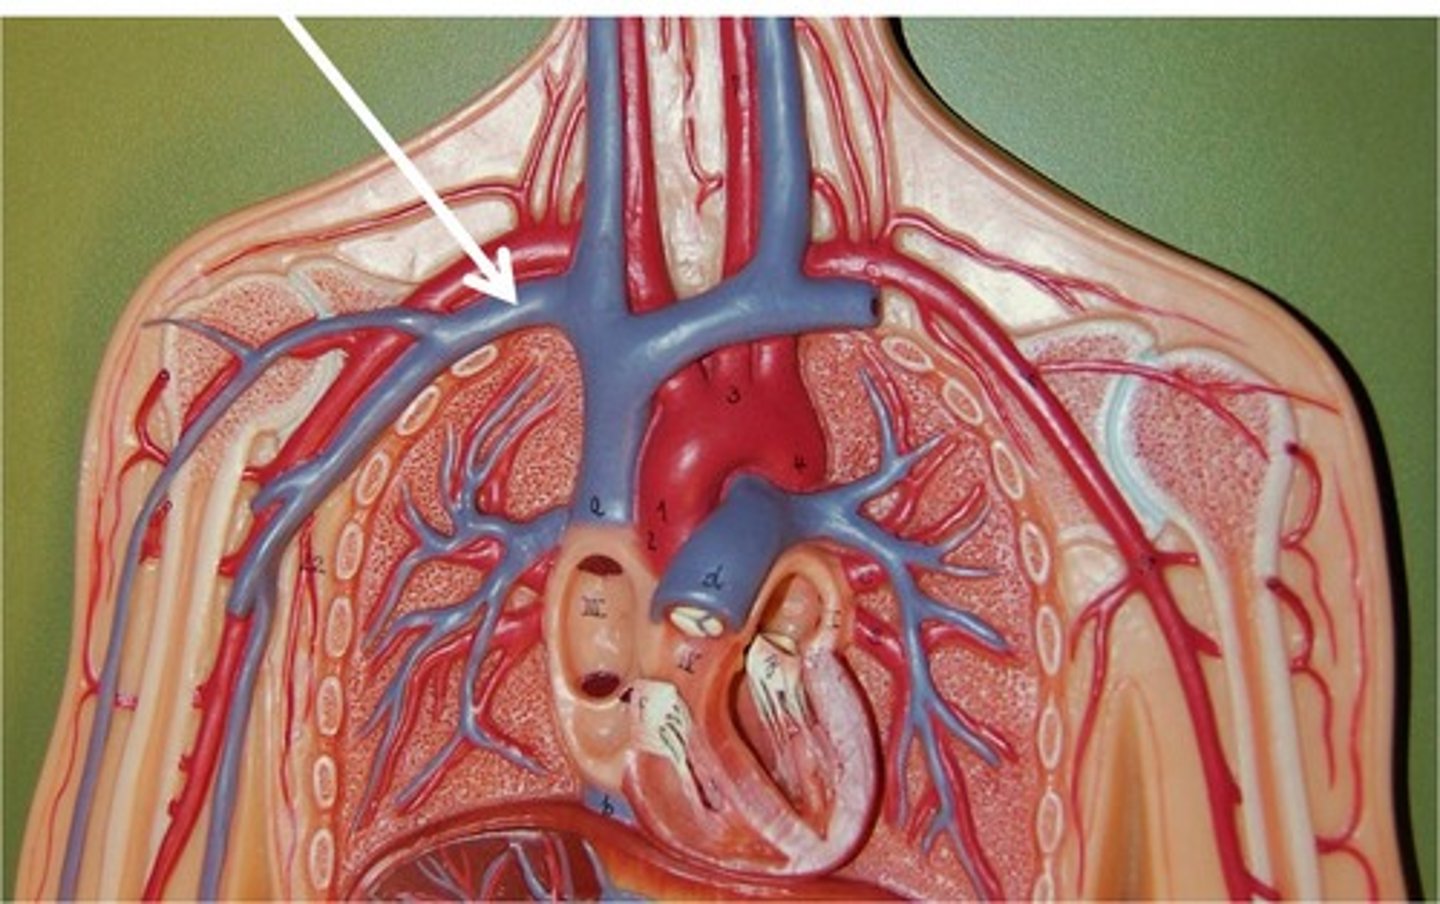

brachiocephalic vein

subclavian vein

superior vena cava